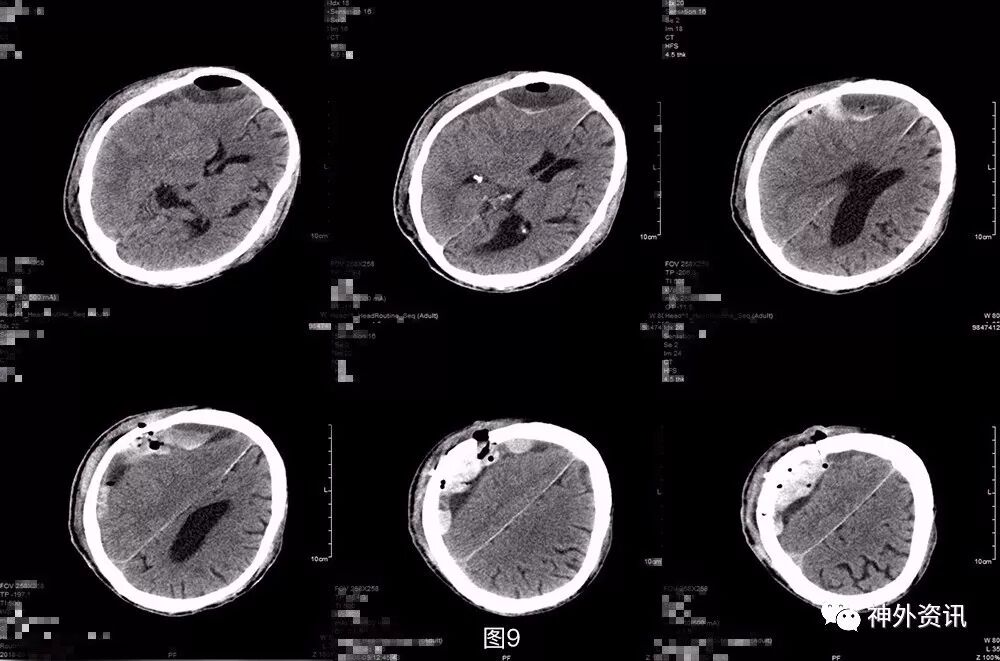

入院后复查头颅CT,提示右侧额颞顶枕硬膜下血肿与上片比较无明显再增大,局部伴积气(图6)。实验室检查凝血功能正常。

图6. 浙医二院术前头颅CT提示:右侧额颞顶枕硬膜下血肿与前片比,基本稳定,局部伴积气。